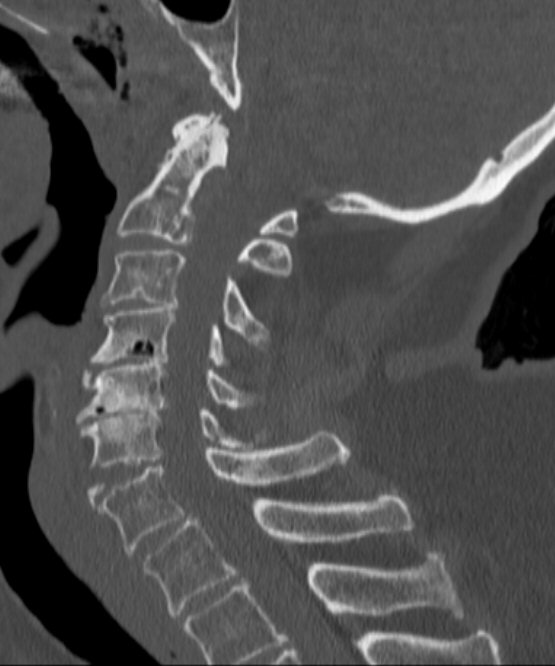

Typiskt äldre patient med degenererad halsrygg som fallit på pannan berusad. DT med diskreta fynd, kan vara helt normal, visa extensions teardrop (se bilder nedan) eller distraktion i disk. Kan vara mycket instabil.

Teardropfrakturer